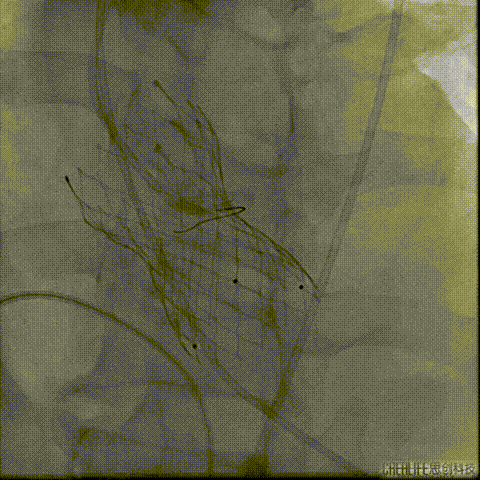

导丝跨瓣及测压

此时患者出现室速 血气提示代谢性酸中毒、高钾血症,予电复率、补碱、补镁、碘氨酮等治疗后恢复窦性心律。